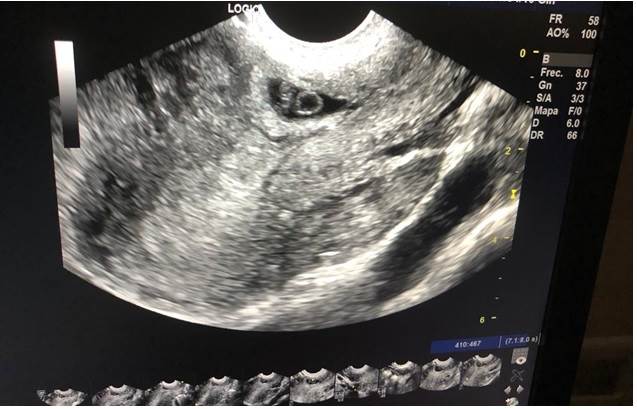

Otro antecedente ginecoobstétrico de interés estuvo dado por que la gestante acudió 19 días antes al servicio de emergencias por presentar dolor pélvico y sangrado vaginal; se establece un diagnóstico de ingreso de embarazo ectópico implantado en histerorrafia (corroborado mediante ecografía (Figura 1) en la que se visualiza saco gestacional regular con presencia de embrión de 6 semanas de gestación en su interior con latido cardíaco) más amenaza de aborto, se indicó maduración cervical, observación con revaloración e inicia tratamiento farmacológico con metotrexato (dos dosis) y cloruro de potasio. Cinco días después solicitó el alta voluntaria, pero reingresa ese mismo día con dolor abdominal en mesogastrio, los exámenes mostraron β-HCG en 13732, por lo que se decidió mantenerla en observación con antibióticoterapia, antes de proceder al alta con indicación de control en 8 días y nueva β-HCG.